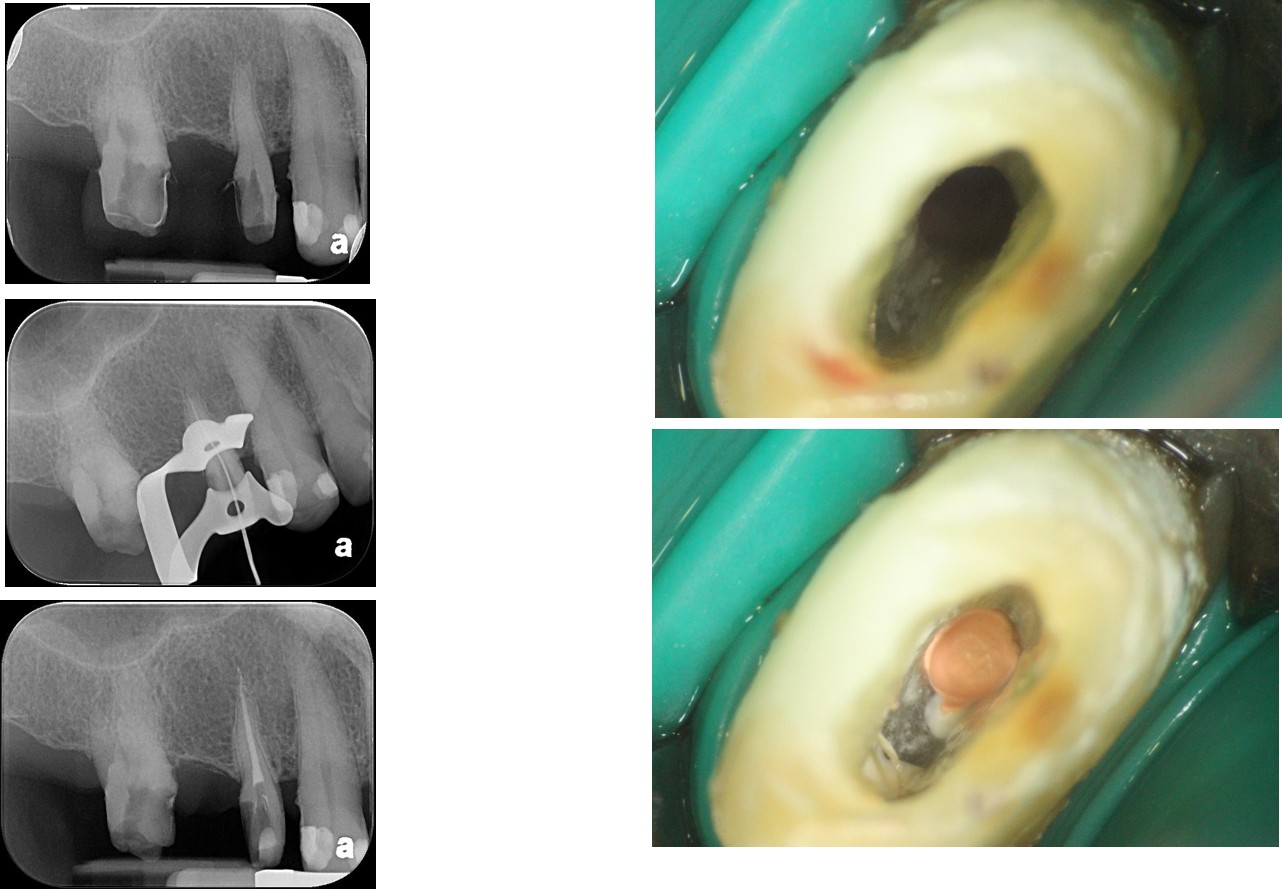

小臼齒顯微根管治療

鑄造金屬釘柱